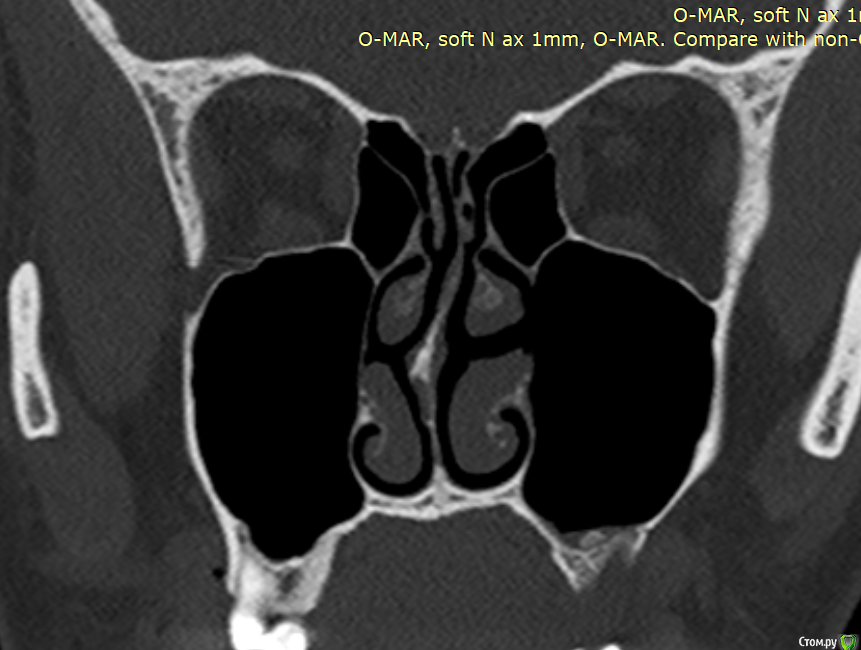

Фрагмент кости в гайморовой пазухе. Нет гноя. Причина болей?

Здравствуйте. На протяжении 5 месяцев беспокоит боль в области между левой пазухой и челюстью. Боль острая, ноющая как при боли в зубе. Верхняя 7а слева (депульпированная) удалена месяц назад, но боль только усилилась. Со временем стали болеть и все суставы в теле, в особенности руки и ноги. Выполнять простые движение стало очень больно. На КТ видны инородные фрагменты и нарушение целостности нижней стенки пазухи, но в Спб никто их не захотел удалять инородные фрагменты из-за того, что причина боли по мнению врачей не в этом. В результате боль только усиливается. Причину боли при моей картине КТ никто установить не может. Обращалась почти во все клиники. Несколько неврологов патологию лицевого нерва исключили. Все это время держится температура 37-37,5. Ощущение сильного воспалительного процесса, боль немного стихает на приеме антибиотиков, но ненадолго, примерно на неделю - две. Обычные обезболивающие совершенно не помогают. Жевать пищу очень больно, сильно рот не открыть. Слабость и нет аппетита. Может ли так организм реагировать на инородный фрагмент кости в пазухе или дело в другом? Возможно ли что есть какие-то нарушения (переломы, трещины и пр) кости, которые требуют хирургического вмешательства?Вопрос возник по той причине, что при промывании пазухи есть ощущение проникания жидкости куда-то за пределы слизистой и после промывания состояние заметно ухудшается. Если кто-то может помочь советом буду очень признательна. Есть несколько КТ 3д. https://yadi.sk/d/PX30GoO1Cn5m_w -  от 13.06.2020 (примерно сразу после появления болевого синдрома), https://yadi.sk/d/bm7FD9SYVw2-Gw- сразу перед удалением зуба,  https://yadi.sk/d/fbaOTQT2-ya4xQ - КТ пазух от 21.11.2020 (то что есть на сегодня).